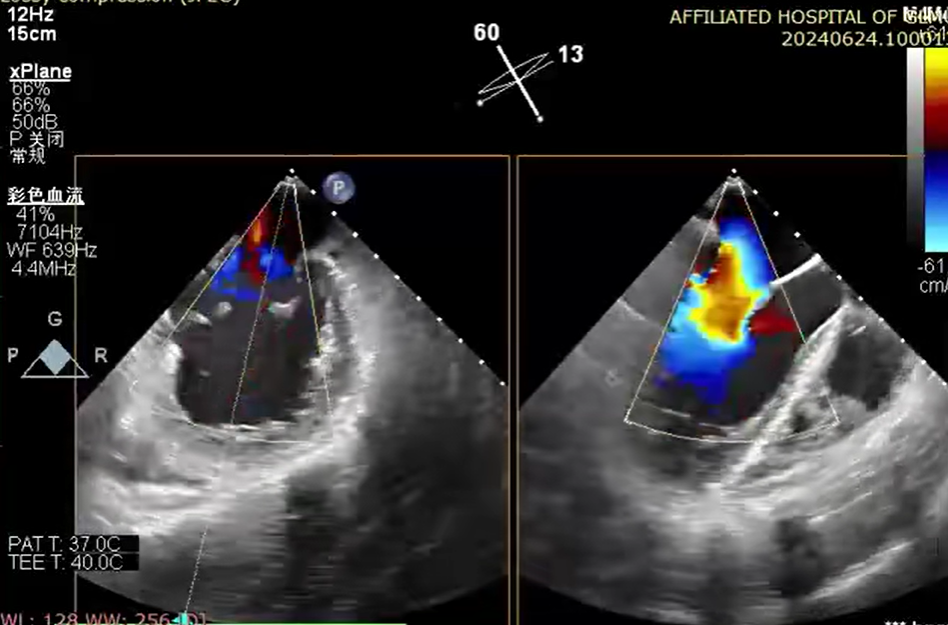

6 月 24 日,心血管内科一病区廖发荣、何武金团队在中山大学附属第一医院庄晓东教授的指导下,在患者右侧腹股沟区穿刺一个 3-5 毫米的小创口,然后将器械通过股静脉穿刺房间隔,把「二尖瓣夹系统」送入患者左心房,进而到达心脏的二尖瓣口,然后全程在食道三维超声引导下,精准夹合二尖瓣后瓣病变区域。

钳夹后,二尖瓣反流从术前 4+改善至 1+、夹合稳定、平均跨瓣压差 2 mmHg,患者术后心功能得到明显改善,无相关并发症,于 6 月 29 日顺利出院。7 月 12 日,患者到医院复查各项生理指标基本正常。